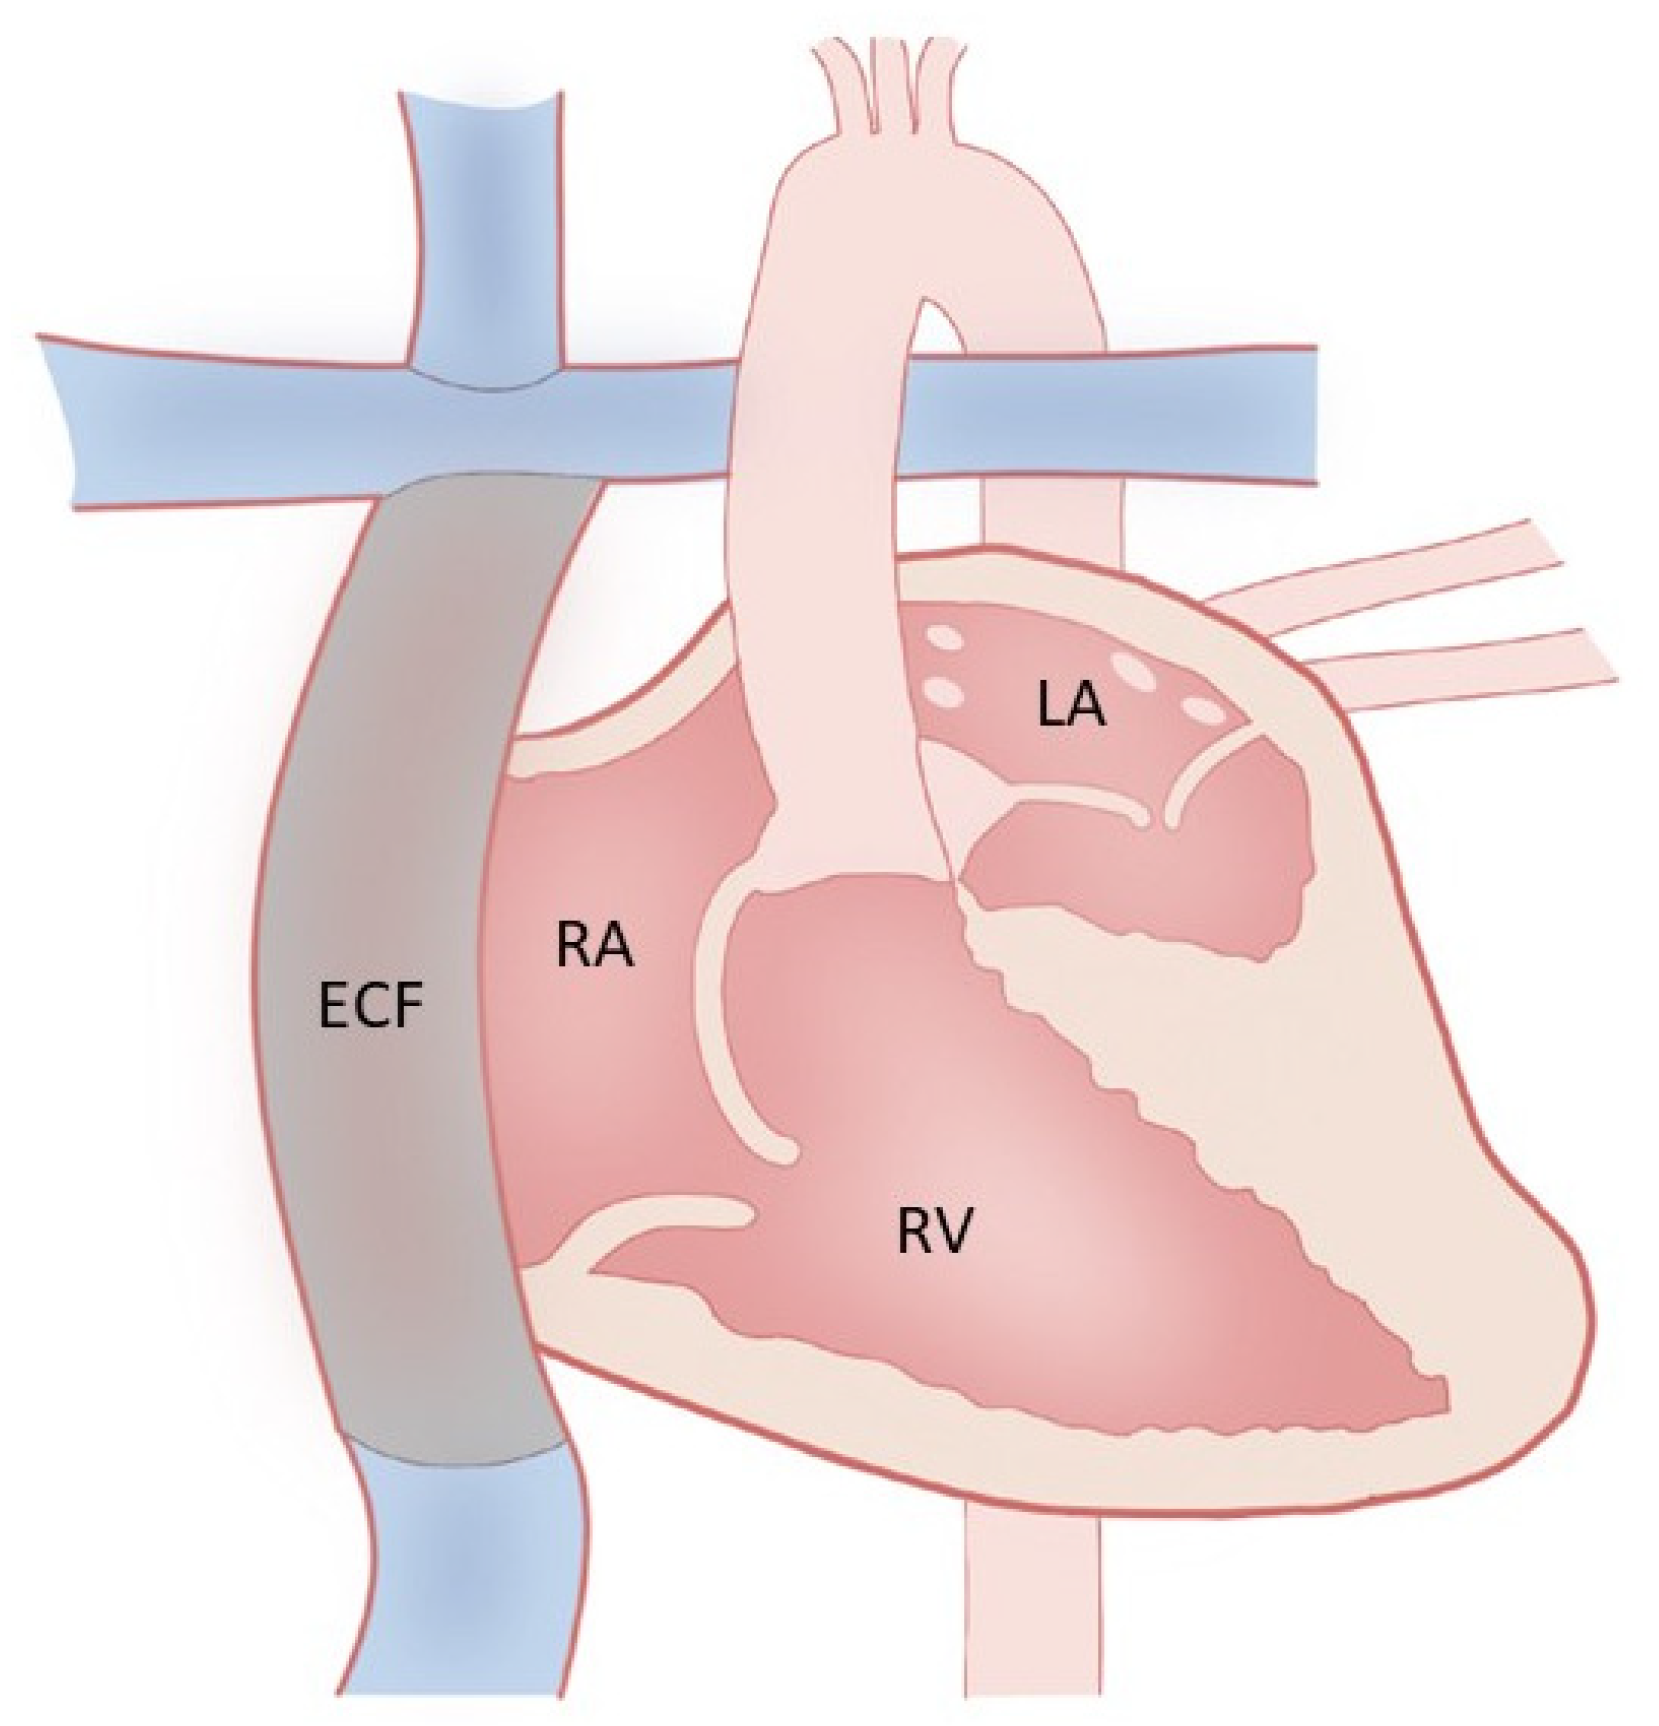

3. Fontan Palliation and Why

4. Fontan Physiology and Failure

18. Advanced Therapies for Heart Failure

19. Mechanical Circulatory Support